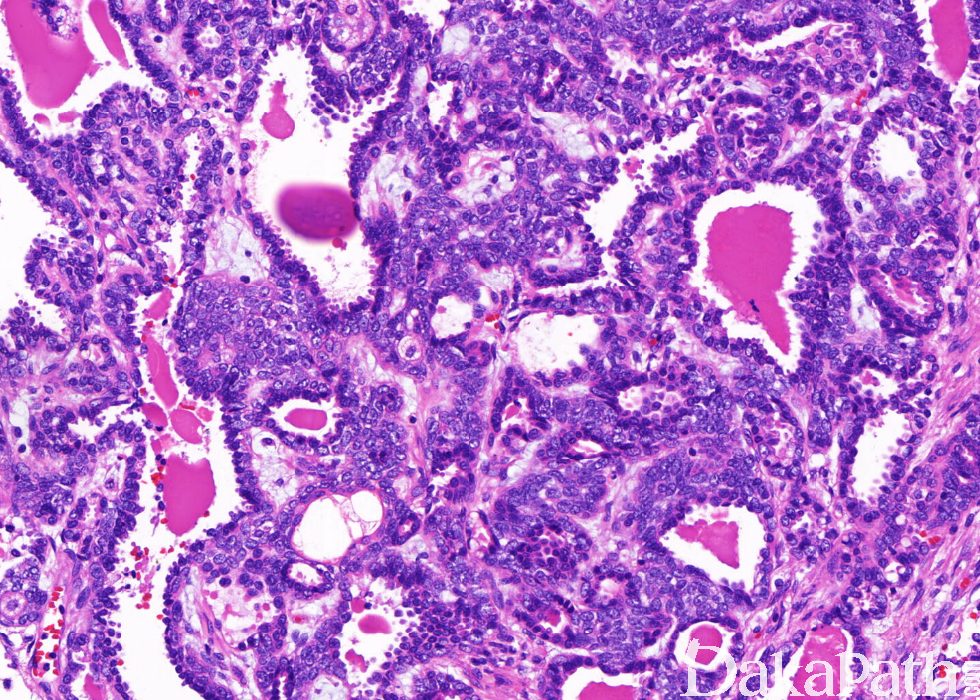

由两种细胞不同比例混合组成管状结构,偶可形成实性细胞巢;

典型的导管由双层细胞衬附,由伴有嗜酸性胞浆的立方形内层细胞和伴有明显透明胞浆的外层细胞组成;

肌上皮细胞有时呈梭形,其增生形成实性细胞巢,其间很少腺上皮,甚至完全由肌上皮组成;

核分裂活性一般很低,很少有坏死;